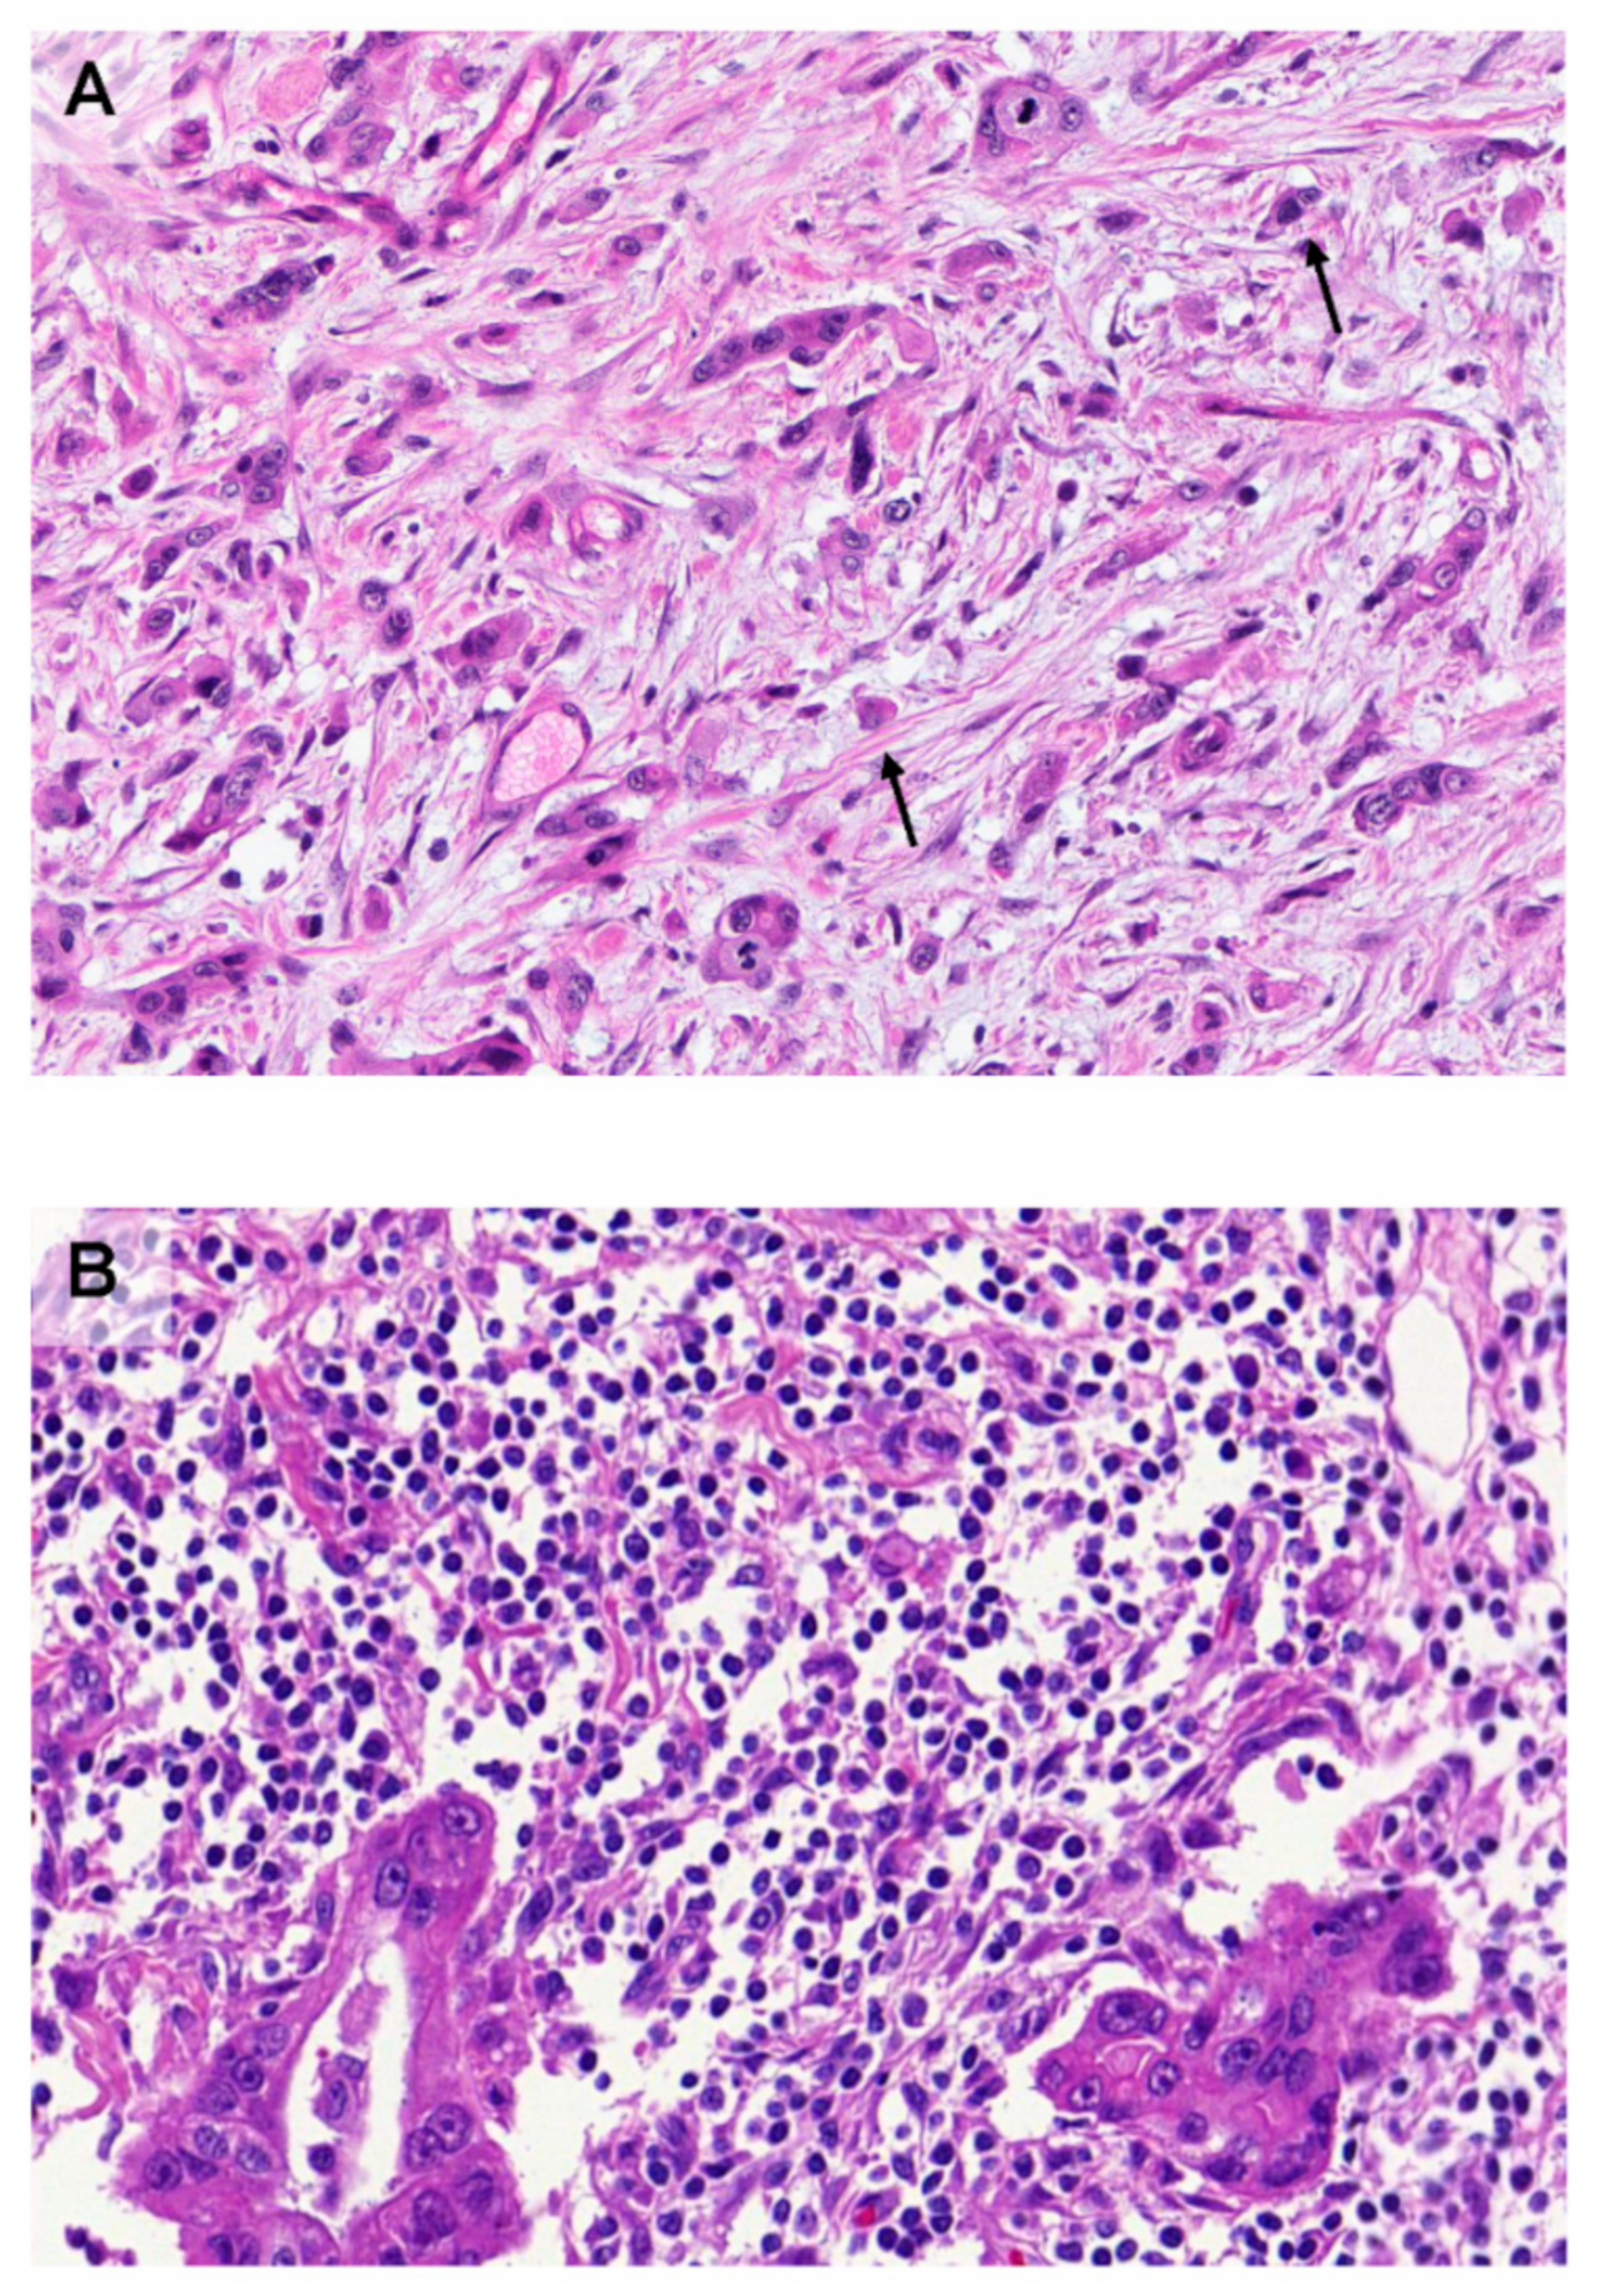

3. Morphology Matters: The Important Role of Tumor Budding

- Galván, J.A.; Zlobec, I.; Wartenberg, M.; Lugli, A.; Gloor, B.; Perren, A.; Karamitopoulou, E. Expression of E-cadherin repressors SNAIL, ZEB1 and ZEB2 by tumour and stromal cells influences tumour-budding phenotype and suggests heterogeneity of stromal cells in pancreatic cancer. Br. J. Cancer 2015, 112, 1944–1950. [Google Scholar] [CrossRef] [PubMed]

- Grigore, A.D.; Jolly, M.K.; Jia, D.; Farach-Carson, M.C.; Levine, H. Tumor budding: The name is EMT. Partial EMT. J. Clin. Med. 2016, 5, 51. [Google Scholar] [CrossRef]

- Karamitopoulou, E.; Haemmig, S.; Baumgartner, U.; Schlup, C.; Wartenberg, M.; Vassella, E. MicroRNA dysregulation in the tumor microenvironment influences the phenotype of pancreatic cancer. Mod. Pathol. 2017, 30, 1116–1125. [Google Scholar] [CrossRef]

- Wartenberg, M.; Zlobec, I.; Perren, A.; Koelzer, V.H.; Lugli, A.; Karamitopoulou, E. Accumulation of FOXP3+T-cells in the tumor microenvironment is associated with an epithelial-mesenchymal-transition-type tumor budding phenotype and is an independent prognostic factor in surgically resected pancreatic ductal adenocarcinoma. Oncotarget 2015, 6, 4190–4201. [Google Scholar] [CrossRef]